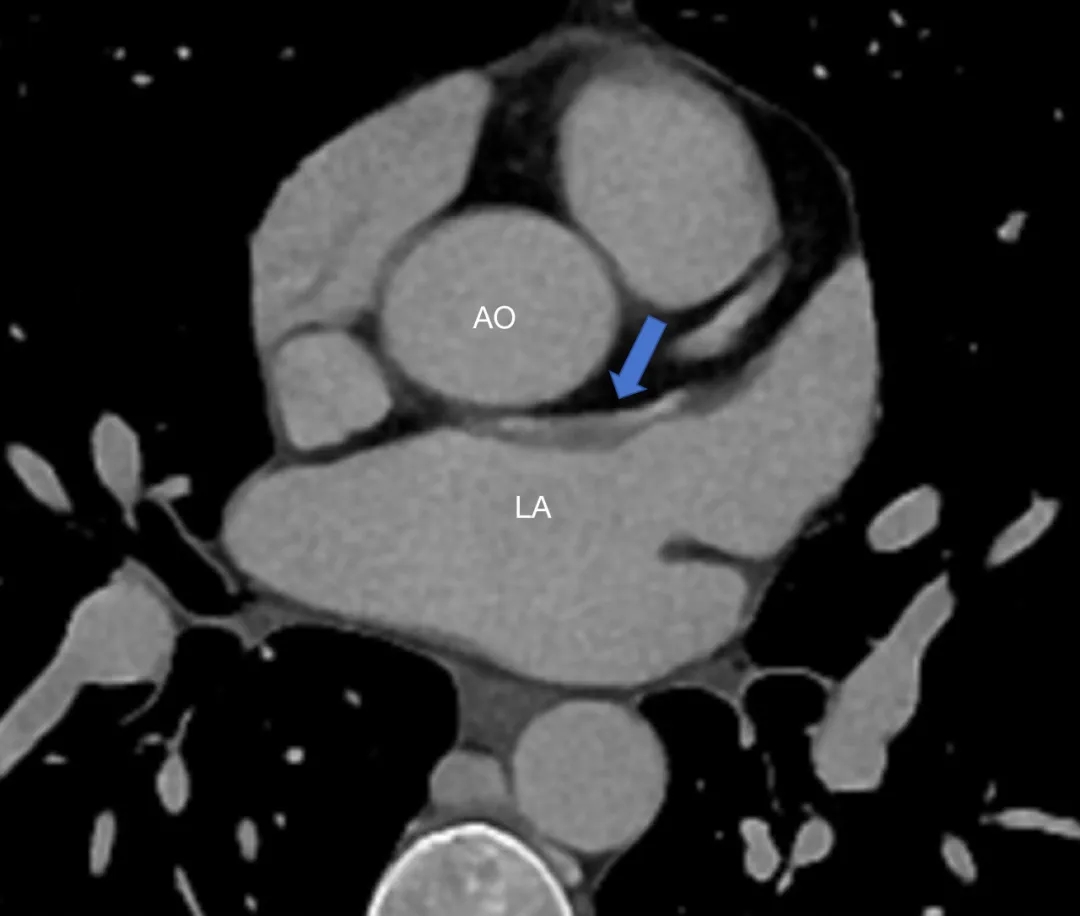

患者女性,27岁,因“卵圆孔未闭相关卒中”入院,拟行介入封堵术。术中MPA1导管跨越卵圆孔进入左心房后送入超滑导丝,发现导丝经由冠状静脉窦走行区回到右心房内,考虑导管进入异常通道,进一步造影可见一起自左心房前壁的冠状静脉分支血管沿房间隔水平横行走行,造影剂最终汇入冠状静脉窦,引流入右心房(图1&2,视频1&2)。该病情血液动力学类似冠状静脉无顶综合征/房间隔缺损,同期行右心导管测肺动脉平均压16mmHg,QP/QS=1.0,排除具有血液动力学意义的左向右分流。由于无法立刻明确单纯封堵PFO的收益与风险,遂终止手术先行完成心脏增强CT明确病变解剖情况,增强CT(图3&4)及重建结果(图5&6)与造影一致,可见一冠状静脉分支起自左心房并沿房间隔走行最终汇入冠状静脉窦。考虑到患者的临床症状可能与PFO以及该异常静脉均存在相关性,且尚不能明确单纯封堵PFO的收益以及同期封堵该静脉的风险,与患者充分沟通后暂时选择最优药物治疗并保持密切随访。

图3